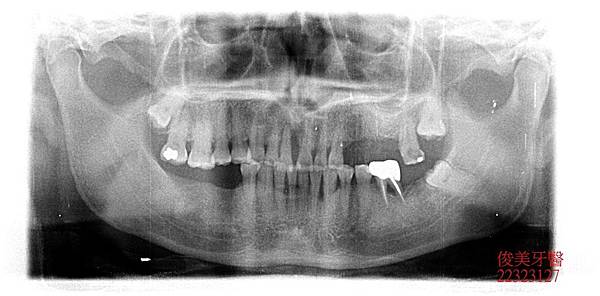

智齒拔除實例

患者為男性,於門診中表示,門牙在搖晃,且後面沒有牙齒可以咬東西,希望可以重建牙齒; 經醫師評估後,因患者有咬合問題,因此建議患者做全口重建,並做矯正調整咬合,患者表示 :因做生意沒有時間做矯正,希望可以療程縮短,可以咀嚼就好,因此醫師調整療程,但要求 患者下顎埋伏智齒因有影響,一定要拔除。 患者同意了。

因患者非常怕痛,先安排重建手術,建立患者信心。 再安排時間拔除智齒。

因年紀已超過40歲以上,且患者的智齒非常壯大,因此手術花了不少時間。 術後患者需冰敷3天,並加強傷口清潔。